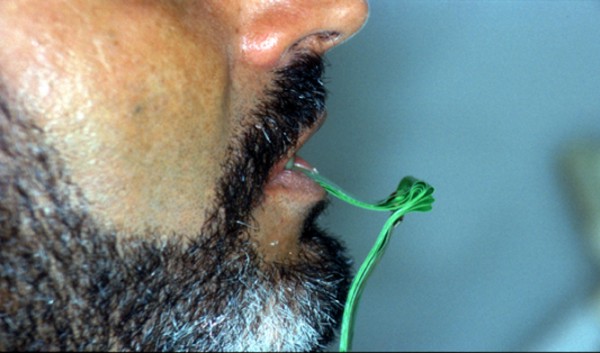

INTRODUCCIÓN El Bruxismo como entidad somática asociada al stress, responde a la mecánica de un Círculo Vicioso Patogénico, que Kawamura describiera hace ya muchos años. FACTOR DESENCADENANTE , que proveen las Interferencias a nivel dentario. En las entregas anteriores se desarrollaron las bases conceptuales de una OCLUSIÓN ORGÁNICA y los efectos de una mayor o menor Desoclusión según la variabilidad de los diferentes Factores Determinantes de la Oclusión. En síntesis; A-La obtención de una Oclusión en Relación Céntrica, nos permite devolver al sistema una elongación muscular fisiológica, sin acortamientos ni estiramientos musculares, sin las consecuentes estimulaciones de los husos neuro musculares, y; una situación estable de la A.T.M. con espacios articulares uniformes. B-El logro de una Guía Anterior que permita desocluir los sectores posteriores durante los movimientos excursivos, nos provée de una segunda y preponderante senda a transitar, que NO estimula por sus contactos excursivos la cincha Pterigo Maseterina, causante de las enormes destrucciones parafuncionales que es frecuente ver en bocas bruxómanas, y la axialización de las fuerzas sobre las piezas posteriores durante el cierre. C-Otorgando como consecuencia, Estabilidad a la tabla premolar-molar, simultaneidad en la recepción de fuerzas durante el cierre(A.T.M. y superficies oclusales). Obtendremos así una Oclusión estable y fisiológica, que no genere el FACTOR DESENCADENANTE del Bruxismo, siempre presente a nivel dentario. INTRODUCTION Bruxism as a somatic entity associated with stress responds to the mechanics of a Pathogenic Vicious Circle, described by Kawamura many years ago. Summarsing: A-Obtaining an oclusion in a Central Relation, allows us to return to the sistem a physiological muscular elongation, without muscular shotthenings or lenghthenings, without the following stimulations of the neuro-muscular huses and a stable situation of the Temporo Mandibular Joint with uniform articular spaces. B-The accomplishment of an Anterior Wide wich may allow disclusive the posterior sectors during the excursives movements, and the axial forces during the mandibular closure. C-Providing as a consecuence, axiality and stability to the posterior sections, responsible of the mandibular closure, through Sttopers, Equalitzers, A, B and C, to obtain a Oclusión Mutuamente Compartida: forces reception during mandibular closure (T.M.J. and Oclusal Surfaces) By this procedure, we should obtain a stable and physiological oclusion, that will not generate the chain link of factors that lead to Bruxism, always present at the dental level. MATERIALES Y MÉTODOS: La funciones articular y muscular, se analizaron mediante Bio Pack, en el pre, en el intra y en el post operatorio. Durante el diagnóstico, tratamiento y remontas, se utilizaron articuladores semi ajustables Wip Mix, totalmente ajustables Artex y arcos faciales correspondientes. El encerado de dianóstico se realizó, mediante la técnica de encerado progresivo de Peter K. Thomas. Los refuerzos a Perno Colado se llevaron a cabo con oro BIODENT YELLOW de ARGEDEN. Los tres juegos de provisionales utilizados, se hicieron con metacrilato termo curado. Las Restauraciones Periféricas Totales, fueron realizadas mediante porcelana CREATION de WILLY GUÉLLER, sobre oro BIODEN YELLOW de ARGEDEN. Los chequeos de los Contactos Interoclusales, se midieron con papeles de articular de 40 y 12 micrones, y mediante el analizador computarizado T-Scan. DESARROLLO Paciente varón de raza blanca, 42 años, complexión robusta y marcada hipertrofia maseterina. Fig.1 Fig.2 Fig.5 Se realiza un análisis pre-operatorio articular y muscular mediante Bio Pack, y oclusal mediante T-Scan, cuyos resultados muestran una evidente hiperactividad muscular en Temporal Anterior y Masetero Derechos, y contactos totalmente anómalos tanto en Oclusión Habitual como en Excéntricas. Fig. 6-7-8-9-10-11 Sensor de ruidos articulares Luego del primer intento de relajación mediante Laminillas de Long (Ref.6),Fig.12, registros y montaje, se observa la aparente presencia de una relación Borde a Borde, que luego se comprobaría que se trataba de una propulsión exagerada de su mandíbula en la búsqueda de contactos efectivos. Fig. 13-14 (Obsérvese el fenómeno de Patterson dado por la exclusiva guía de movimiento de la A.T.M. y la carencia de la Guía Anterior) Se procede a construir un JIG de LUCIA para lograr una desprogramación muscular adecuada, y se le indica permanecer con el colocado durante toda la noche anterior a la consulta, sin contactos dentarios posteriores. Aún en la duda, de que la obtenida sea una posición articular fisiológica, se procede a construir una Placa de Relajación sobre el último montaje obtenido, la que se ajusta cada dos días, y al cabo de tres semanas se procede a un tercer montaje obtenido de la nueva situación posicional. Fig.17-18 Se verifica entonces que estamos en realidad, ante una presunta CLASE II, después de tres métodos diferentes de relajación y transcurridos más de un més de múltiples sesiones para lograr una posición diagnóstica confiable a partir de donde comenzar a trabajar.(O.R.C.) Se adicionan entonces topes (montículos) en las caras oclusales de los primeros molares de la Placa de relajación, transformándola en una Férula Pivotante, de levísima altura, impidiendo el contacto de las demás piezas dentarias a fin de convertir la palanca en una de clase II (fisiológicamente el sistema se mueve según una palanca de clase III), y obtener de esa forma una descompresión de los espacios articulares, ya que si bien la A.T.M. era asintomática, estaba muy claro que la Dimensión Vertical Posterior se presentaba disminuida debido al exagerado desgaste de todos los sectores posteriores, cuya típica forma de «desgaste en olla», se verificaba en el análisis estático de los modelos.( Ref.7) En esa situación se remonta el modelo inferior puesto que el superior no modifica su posición espacial, y se realiza un Encerado de Progresivo Diagnóstico según PKT, previo análisis de los modelos mediante los analizadores de W.McHorris (Ref.8) Fig.18-19-20-21-22-23-24-25-26-27-28-29-30 Fig.18 Fig.22 Fig.23 (Obsérvese, que la Disclusión Propulsiva comienza en los rebordes mesiales del canino, sigue en los rebordes distales del lateral, y finaliza con los rebordes mesiales de los centrales.) Se realizan las endodoncias de toda la boca y se tallan los endodontos para la construcción de Pernos Muñones Colados de oro, los que se realizarán mediante técnica indirecta sobre los modelos :montados según los logros de todos los procedimientos de relajación. Se torna imprescindible la extracción de tres piezas dentarias, para la confección de la Guía Anterior, cuyo alineamiento hubiera sido imposible mediante técnicas reconstructivas ya que la posibilidad ortodóntica no era viable dadas las condiciones de desgaste. Fig.31-32-33-34-35-36-37 (Obsérvese, que desde la configuración de los Pernos Muñones Colados, se determina ya la Alineación Tridimensional que otorgaremos a la Rehabilitación Oral Integral del caso. Se monta entonces el primer juego de Provisionales de acrílico de termo curado, obtenido de la réplica del Encerado de Diagnóstico. Fig.38-39-40-41 (Obsérvese la presencia del ajuste periférico y las disclusiones, tan importantes en las provisorias como en las definitivas ya que del resultado de la etapa de provisionales, dependerá el éxito final.) Se ajustan las Unidades de Oclusión mediante Ajuste Oclusal (según técnica propuesta por la Cátedra de Operatoria Dental II y Prótesis de la Fac. de Odontología, Univ. Bs. As., Prof.Anibal Alonso.) Se deja actuando la nueva situación durante seis meses. Han transcurrido seis meses durante los cuales se instaló un nuevo juego de provisorios con las mismas características del anterior, y clinicamente no se observa hiperactividad muscular, perforaciones de los provisorios, molestias para desmenuzar los alimentos ni síntomas alguno en la A.T.M. NOS ENCONTRAMOS, CON UN SISTEMA EN PAZ A TODOS SUS NIVELES. Se procede entonces a la toma de impresiones definitivas, mediante la técnica de Impresión a Presión Masticatoria, para la confección de las restauraciones permanentes, y los metales se chequean mediante llaves de Duralay, para observar la situación análoga entre laboratorio y clínica.(Corroboración de la Oclusión en Relación Céntrica)Fig.42-43-44 Se prueban los metales y verifica su ajuste periférico. (Obsérvese que también en los metales sub porcelana se siguen las formas de las Preparaciones Funcionales, permitiendo de esta manera un perfecto bizcochado de la porcelana supra metal.) Realizada la Guía Anterior, Determinante Oclusal Primario y Anterior en el laboratorio, se prueban en boca sus características estáticas: Altura Funcional, Ángulo de la Disclusión y Punto de Acoplamiento, como así las dinámicas: Laterotrusión Derecha e Izquierda y Propulsión. En este estado las cosas, tenemos al sistema circunscripto tanto estática, como dinámicamente, por el gobierno de dos comandos, ya en Oclusión en Relación Céntrica, como en las Transtrusiones: Sabemos que todo lo que construyamos (tabla premolar-molar), entre estos dos comandos rectores del movimiento, partirán del mismo punto y volverán a el, transitando el recorrido impuesto por los mismos. Se construyen entonces en el laboratorio, las unidades de oclusión de premolares y molares, siendo las correspondientes a los cuatro últimos molares, con oclusal en oro, como un elemento de detención del cierre más poderoso que la porcelana.47-48-49-50-51 Se prueban en boca la Curva de Wilson, la Curva de Spee, la Alineación Tridimensional, los Espacios Uniformes Disclusivos, la Dirección de los Surcos de T, nT, y P, y los Puntos Interoclusales de Contacto. En laboratorio se retocan entonces los Puntos Interoclusales de contacto, acercando los mismo a la mejor posición ideal lograble, y luego de una nueva prueba en boca, se glacéan las piezas y se instalan en forma provisional durante 24 hs. Verificada la eficacia de las formas (FORMA=FUNCIÓN), se procede a constatar la eficiencia de la dinámica trayectorial y se cementan con cemento de fosfato mediante la técnica de cementado alterno. Fig.54-55-56-57-58-59-60-61-62-63-64-65-66-67-68-69. Fig.54 Fig.55 Curva de Wilson y Alineación Tridimensional en molares y premolares sup. Der. Fig.56 Fig.57 idem inferiores derechos Fig.58 Fig.59 Idem superiores izquierdos CONTACTOS INTEROCLUSALES SUPERIORES CONTACTOS INTEROCLUSALES INFERIORES Transcurrido un mes de instalada la Rehabilitación, se lleva a cabo un nuevo estudio, post operatorio con Bio Pack y Tscan. CONCLUSIONES : I-El paciente realiza una apertura bucal de 45mm sin forzamientos siguiendo una misma línea de apertura sin desvíos. II-Las disclusiones en laterotrusión se llevan a cabo mediante un recorrido lineal sobre los rebordes medios de ambos caninos superiores, creando un fenómeno de Luce con espacios uniformes en ambos lados. III-La disclusión en propulsión se manifiesta comenzando en los rebordes mesiales de ambos caninos, siguiendo por los rebordes distales de laterales y terminando en los rebordes mesiales de ambos centrales, dando lugar a un fenómeno de Christensen con espacios uniformes de ambos lados. IV-Los contactos interoclusales son suficientes, simultáneos y tripódicos logrando la estabilidad en ambos planos del espacio tanto de las piezas individuales como en conjunto, sin contactos deflectivos. V-Realizado un nuevo montaje de la boca terminada, corroboramos como estable la Oclusión en Relación Céntrica. VI-No existen movilidades dentarias y los tejidos periodontales y gingivales se encuentran estabilizados. VII-No existen ruidos articulares. VIII-El resultado post operatorio Bio Pack de la dinámica mandibular, muestra una sustancial mejora de los movimientos en los tres planos del espacio. IX-Electromiográficamente, se observan contracciones musculares dentro de los rangos de normalidad, persistiendo un rango ligeramente elevado en temporal anterior y masetero del lado derecho, presumiblemente debido a la hipertrofia que dicho paciente traía, y mostraba en el estudio pre-operatorio. COMPARACIONES PRE, INTRA Y POST OPERATORIAS Sonografía de la ATM: Tanto en el examen pre como post operatorio no se observaron ruidos de ningún tipo, coincidiendo con la exploración clínica pre auricular e intra auricular. Electromiografía: La electromiografía en reposo, muestra bien a las claras la presencia de músculos hipertónicos durante el estudio pre operatorio, fundamentalmente del grupo Temporal Anterior y Digástricos, estando el Masetero izquierdo ligeramente por encima de su rango normal como así también ambos Esternocleidomastoideos. Durante el estudio post operatorio, se verifica el estado tónico de todos los grupos musculares, persistiendo una ligera hipertonicidad de rango levemente por encima de lo fisiológico, en el Temporal Anterior Derecho y Digástrico Derecho. PRE OPERATORIO POST OPERATORIO Temporal Ant. Der. 4.4 2.8 Temporal Ant. Izq. 6.2 1.1 Masetero Der. 1.2 0.5 Masetero Izq. 1.5 0.8 Est.Cleid.Mast. Der. 1.6 0.3 Est.Cleid.Mast. Izq. 2.1 0.2 Digástrico Der. 1.7 2.9 Digástrico Izq. 1.6 0.7 (La unidad de medida utilizada es el microvoltio ) Dinámica mandibular: Durante el Pre Operatorio, en el Plano Sagital, tanto la Apertura como el Cierre lento, se manifiesta mediante una acentuada tendencia a propulsar la mandibula. Durante el Post Operatorio, la tendencia hacia la derecha de estos dos últimos planos se mantiene, mientras que en Plano Sagital, la propulsión inicial no se produce, asemejándose el movimiento a la primera fase del Bicuspóide de Posselt. El Análisis de la Dinámica realizado durante la Masticación (chicle), nos muestra en el Plano Sagital, la propulsión mencionada durante la apertura y cierre lentos durante el estudio Pre Operatorio, se aproxima a la normalidad durante el Intra Operatorio (2º juego de provisionales), y se vuelve a manifestar propulsivo, en el Post Operatorio. En cuanto al Plano Frontal, durante el Pre Op. , ofrece un Ciclo Masticatorio(recordar la forma de «gota de agua») para el lado izq., con componentes derechos e izquierdos alternos, que se aproximan paulatinamente al Ciclo Masticatorio Normal, durante el Intra y Post Operatorio. El Plano horizontal, confirma las afirmaciones anteriores durante los tres períodos de estudio. ANÁLISIS MEDIANTE TSCAN 1-Bio Pack Bio Research Associates,Inc Distrib.UEDA S.A. 2-Wip Mix-Artex 3-Au:89% / Pt:6% /Elementos complementarios:5% 4-Idem ref.3 5-Tscan TekSkan,Inc Distrib.UEDA S.A. 6-Mc Horris.Cátedra de Operatoria Dental II y Prótesis. 7-Alonso.Cátedra de Operatoria Dental II y prótesis. 8-Mc.Horris. Analizadores de Guía Anterior. BIBLIOGRAFÍA: 1-Esquemas de las dos primeras entregas, tomadas del libro:»Oclusión Orgánica…un camino hacia la Rehabilitación Oral» 2-Oclusión y Diagnóstico en Rehabilitación Oral. 3-Anatomia Odontológica. 4-A contribution to the study of the movementes of the mandible. 5-Celenza F.W, Nadeskin J.F.,Oclusión.Situación actual. 6-D´Amico 7-Dawson P.E. 8-Huffman -Regenos. 9-Hobo S.-Takayama H.A. 10-Lucia V.O 11-Mc Horris. 12-Mc Horris. 13-Posselt U. 14-Stuart C. 15-Vartan Veshnilian AGRADECIMIENTOS: La Rehabilitación Oral, especialidad donde se hace imprescindible el manejo y concurrencia de todas las especialidades dentales en su desarrollo más depurado, no tendría razón de ser, sin la más estrecha colaboración de una técnica para- médica con detalles de excelencia. Sr. Pedro Colomina: muchas gracias. Pedro Colomina. – Titulado especialista en prótesis dental en la escuela Ramon y Cajal de Barcelona 1988

Al cabo de los mismos se realiza una nueva comprobación del estado articular y muscular mediante Bio Pack y un chequeo oclusal mediante T-Scan, donde se observan una evidente mejoría de la musculatura comprometida, de la dinámica mandibular, de la apertura bucal, de los contactos simultáneos de la Oclusión en Relación Céntrica como así de las Excéntricas, y un manifiesto control masticatorio por parte del paciente.

Durante esta última, se obtiene un comienzo en los rebordes mesiales caninos, luego los laterales y por último los centrales, tal como se concibió en el encerado.